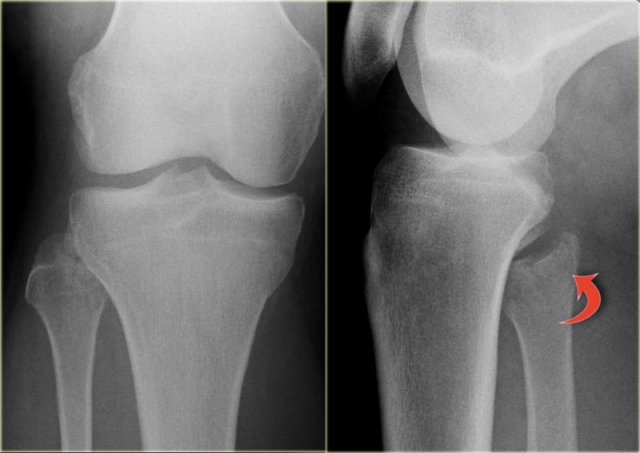

This patient had a twisted ankle and the only abnormality is seen on the lateral view.

This was thought to be an avulsion of the posterior malleolus.

Knowing that this can be the only clue to a high Weber C, additional radiographs were taken.

Continue with the images of the lower leg.

A subtle high fibula fracture is seen (arrow).

Final diagnosis is a Weber C fracture or according to Lauge Hansen: Pronation Exorotation injury stage 4.